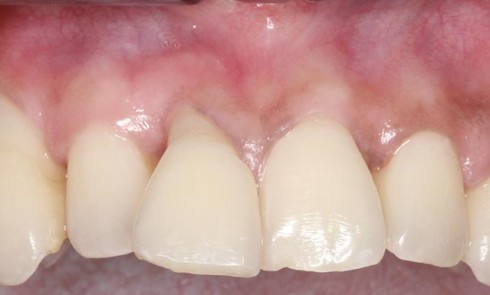

Article réservé à nos abonnés Protocole de mise en charge en 36 heures chez l’édenté total

De nos jours il est presque inconcevable de proposer un traitement implantaire au patient en voie d’édentement au maxillaire sans...